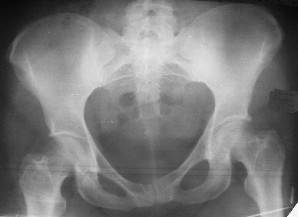

Уважаемые коллеги! Хотел-бы обсудить интерессный, на мой взгляд, случай.На консультацию пришла женщина 45 лет с отводящей контрактурой правого бедра.

Из анамнеза: в ноябре 2002г. оступилась,упалана трап самолета (на верхней площадке, сразу при выходе из салона) на правый тазобедренный сустав, а затем - вниз на землю на ноги и ягодицы. Потеряла сознание от боли. Доставлена в больницу по месту жительства, лечилась консервативно с диагнозом кокцигодиния.На рентгенограмме от 27.11.02г. вывиха копчика не определяется (снимок идентичен представленной R-грамме от28.11.03г., кроме этого есть нормальная R-грамма копчика в боковой проекции).Через три недели стала ходить, но привести правую ногу в тазобедренном суставе не могла. Сейчас ходит отведя кнаружи правое бедро и голень, как ножку циркуля (фото 1). Неврологических нарушений нет. По просьбе врачаможет на 30-40 секунд поставить ноги вместе (фото 2). При этом испытывает сильную тянущую боль и ощущение "вывернутости" в правом тазобедренном суставе. Эти ощущения заставляют вновь отвести бедро. В положении лежа разогнуть бедро полностью не может из-за болей в ягодичной мышце (фото 3). Сгибание также ограничено из-за болей (фото 4). Отведение в положении лежа возможно в том же объеме, что и стоя (фото 5). Заподозрен старый разрыв правого крестцово-подвздошного сочленения.Выполнено R-исследование и КТ(в приложении). По-поводу деформации лонного сочленения выяснен гинекологический анамнез. Роды одни, нормальные в 22 года. Из роддома выписана на 8 сутки, нарушения походки не было, R-графия таза не проводилась. Вопросы на обсуждение: 1. Диагноз либо алгоритм дальнейшего обследования. 2. Лечебная тактика (в первую очередь возможность и целесообразность оперативного лечения).

Уважаемый Юрий Алексеевич, сделаны ли пациентке более дистальные срезы КТ с захватом области тазобедренного сустава? Учитывая давность травмы, могли присоединиться и дистрофические процессы в субхондральной кости головки и впадины. Изменения в капсуле будут хорошо видны на УЗИ, особенно в сравнении со здоровой стороной. Эффективность лечебно-диагностического введения гормональных препаратов, на мой взгляд, сомнительна ввиду давности патологического состояния. При такой стойкой и давней контрактуре без операции вряд ли можно обойтись. Под наркозом амплитуда на разгибание должна увеличиться, усилить эффект можно тено-миотомиями заинтересованных групп мышц, капсулотомией + в послеоперационном периоде хорошее консервативное противовоспатлительное лечение с укладками на разгибание.Что мешает приведению пока не ясно, во встретившихся в нашей работе аналогичных ситуациях причиной был формирующийся медиальный остеофит головки, выталкивающий её из впадины.